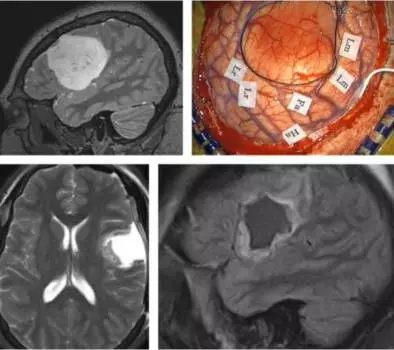

病例1:一名年轻患者因癫痫全身发作就诊,诊断额叶后部巨大低级别胶质瘤。

图10. 图示术前MRI与术中定位(第一行图片)。对运动性语言功能区(Lm),语言接受能力区(Lr),脸(Fa)和手(Ha)区的定位为进一步安全切除肿瘤保驾护航。肿瘤边界如黑色缝线所示。肿瘤深部可采用皮层下定位。笔者将皮层刺激的参数调高1-2mA用以实施皮层下定位。在切除术中,当处理关键皮层及传导束附近区域时,需频繁进行术中监测评估患者状态。这种及时反馈对术者意义非凡,并鼓励术者在刺激定位数据引导下进一步切除肿瘤。

术后影像学示对肿瘤进行了适当的切除(第二行图片),患者未出现任何功能损害。